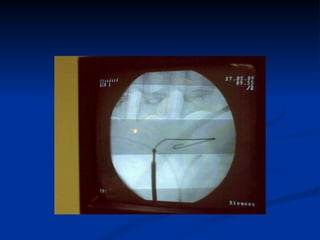

Steps for PCNL Retrograde ureteric catheterization  Fluoroscopy-guided percutaneous puncture(B-ultrasound for simple case) Tract dilation Lithotripsy Double-J stent and nephrostomy tube placement

Retrograde ureteric catheterization 6Fr ureteric catheter open end  Wash out small stones Prevent small stones moving from pelvis into ureter

Steps for PCNLRetrograde ureteric catheterization Fluoroscopy-guided percutaneous puncture(B-ultrasound for simple case) Tract dilation Lithotripsy Double-J stent and nephrostomy tube placement

Retrograde ureteric catheterization6Fr ureteric catheter open end Wash out small stones Prevent small stones moving from pelvis into ureter